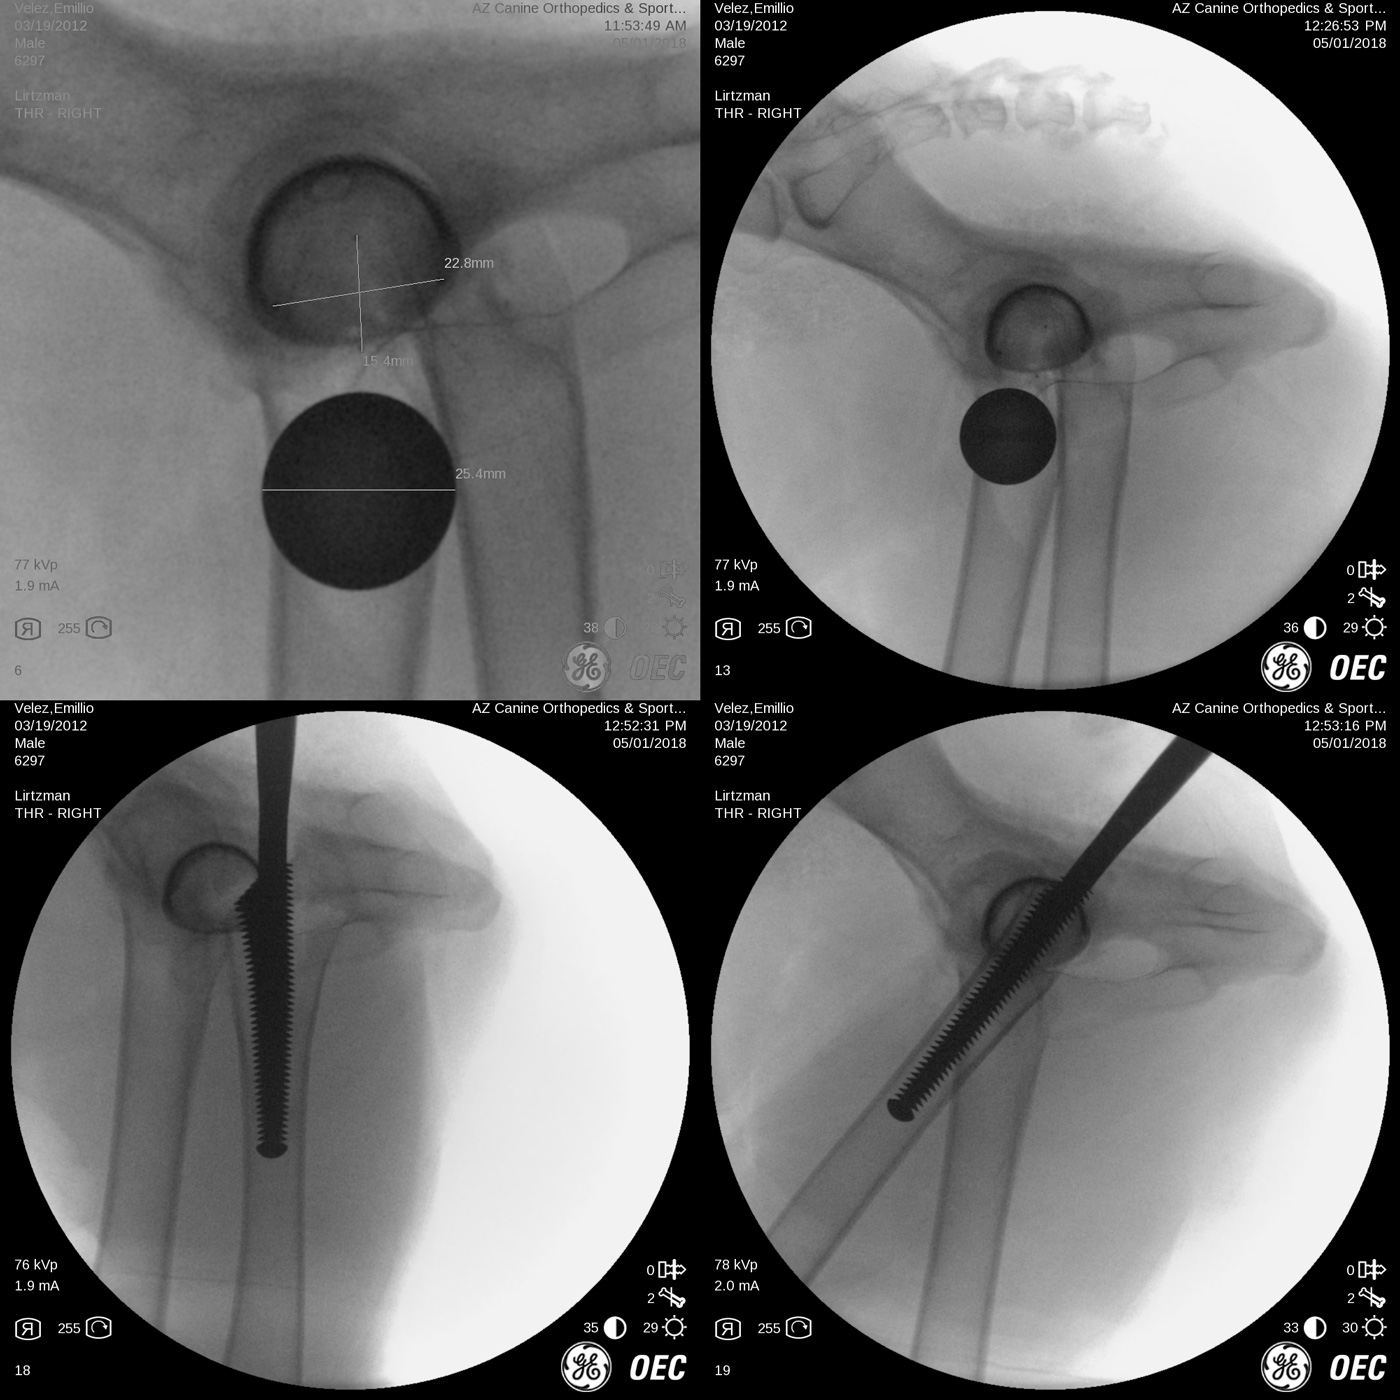

Risk associated with patient malpositioning or movement of the pelvis during surgery, bone preparation techniques, implant sizing and implant postion-orientation have been greatly reduced by the addition of intra-operative x-ray imaging as seen below. The most common and significant problems include:

These are nice examples of Biomedtrix BFX cementless femoral stems. From left, the original tapered stem design to the newer, augmented collared (middle image) and lateral bolt (right) femoral stems.

This is an example of a German Shepherd dog with bilateral, hybrid, total hip replacement (Biomedtrix BFX cementless acetabular cup and CFX cemented femoral stem). Hybrid constructs may be used in certain breeds like the German Shepherd and giant breed dogs, geriatric dogs or those with poor bone quality/thin femoral cortices.